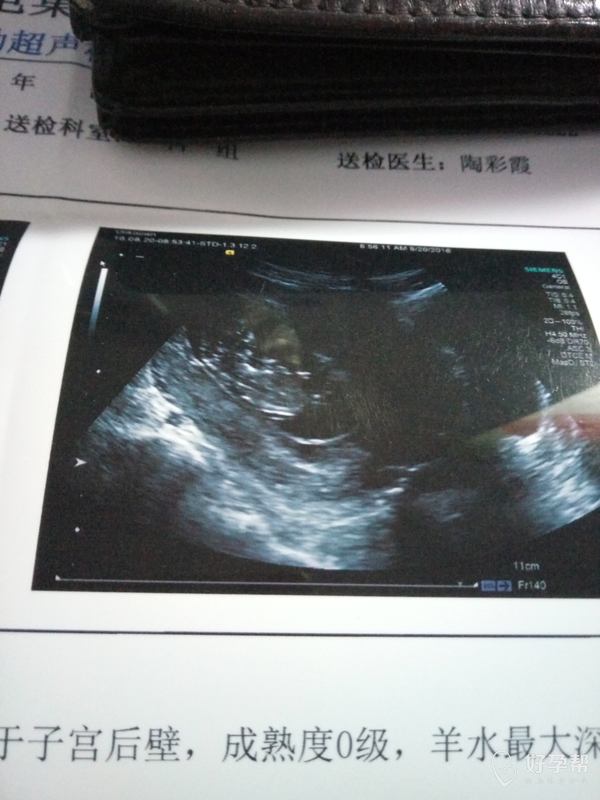

11周 3的b超,偏小吗,宝宝的第二张照片

图片尺寸600x800